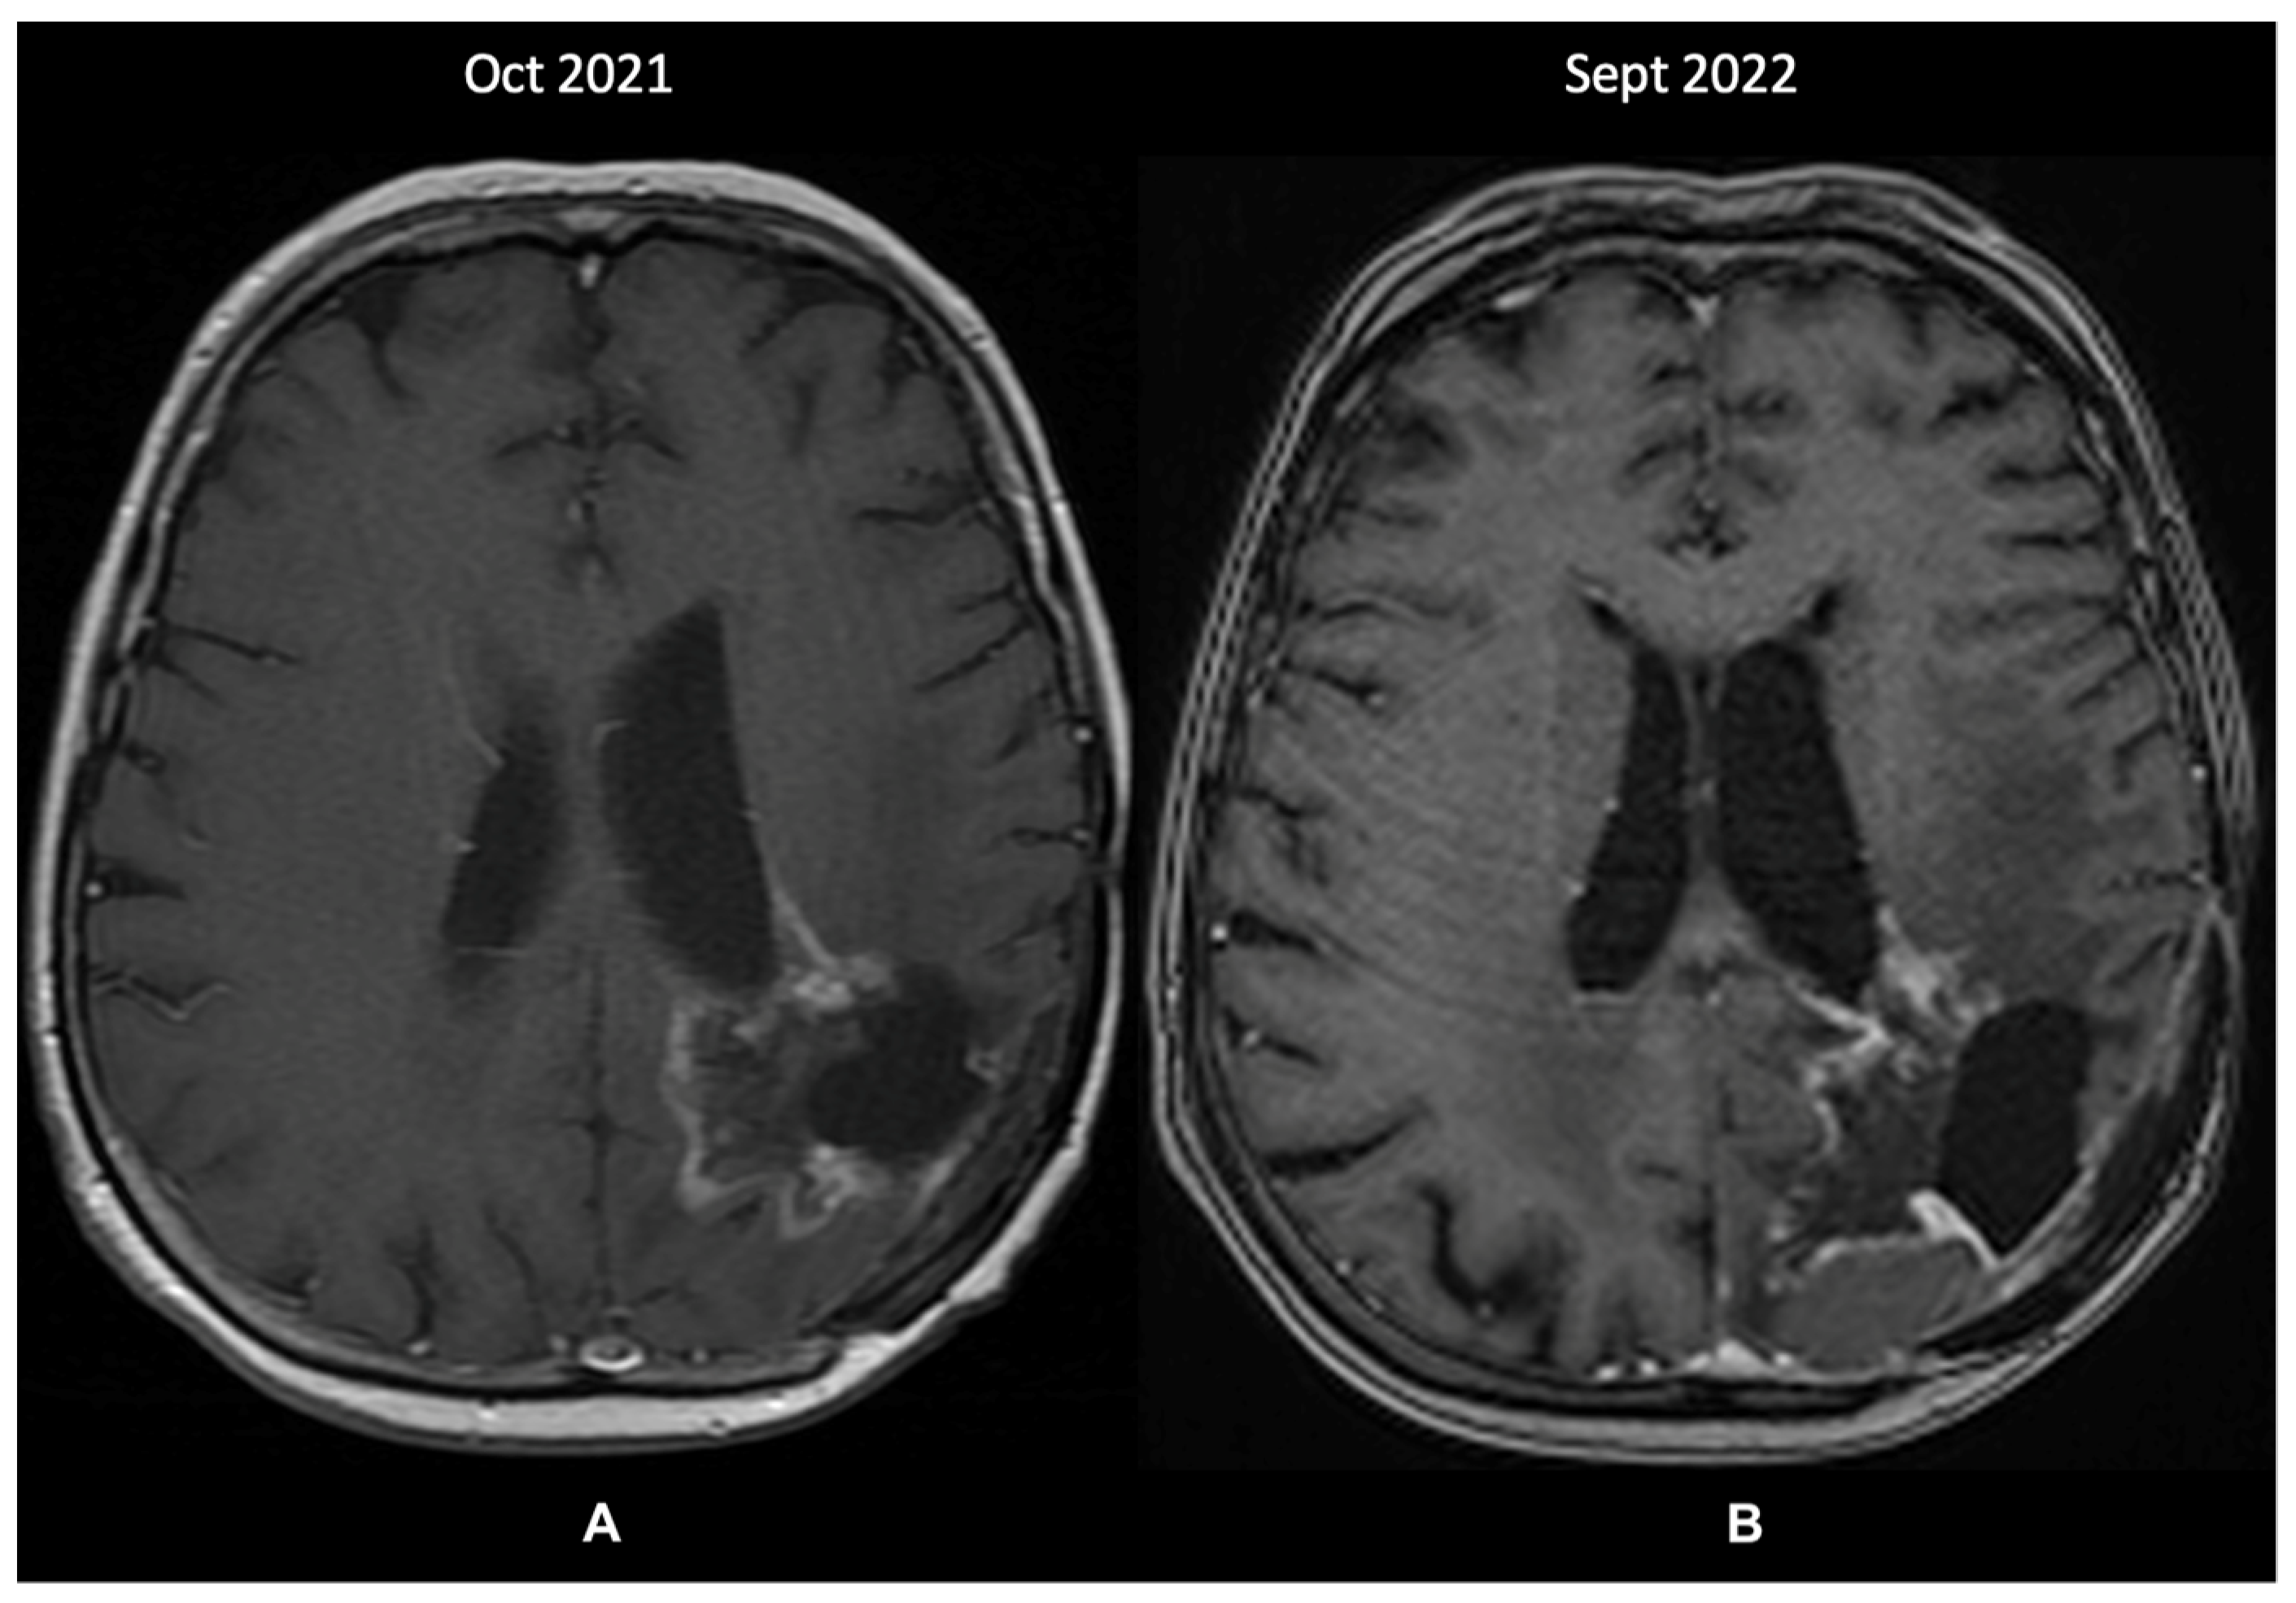

2.2. A Case of Glioblastoma Downstaged Due to the IDH Status